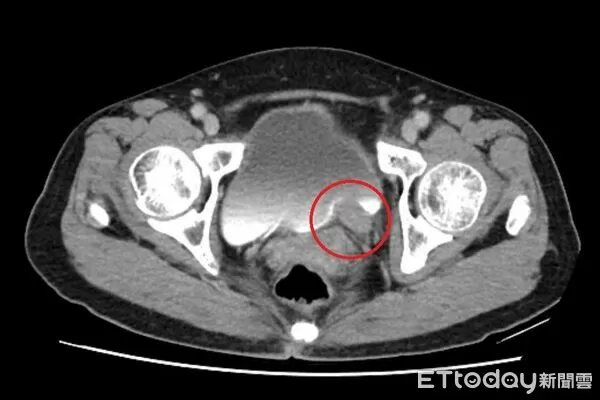

▲一名女性出現無痛性血尿,竟是輸尿管泌尿上皮癌。(圖/院方提供,下同)

67歲的林女士近期出現間歇性的無痛血尿,到醫院檢查發現左側輸尿管末端長了一顆5公分的腫瘤,且有腎水腫情形,確診為「輸尿管泌尿上皮癌」。醫師指出,長期吸菸、處於環境汙染及具家族史者都是危險因子,該癌症狀並不明顯,常見表現為無痛性血尿,若置之不理,腫瘤可能造成阻塞及腎衰竭、遠端轉移。

台北慈濟醫院泌尿科醫師許竣凱指出,輸尿管是連接腎臟與膀胱的重要管道,負責將腎臟產生的尿液順利輸送到膀胱儲存與排出,根據衛福部統計,泌尿上皮癌發生率每十萬人中約有40~50例,臨床上會以尿液檢驗、膀胱鏡、超音波與電腦斷層進行診斷,排除泌尿道感染、輸尿管結石等會伴隨疼痛的血尿後,就要高度懷疑腫瘤的可能。

許竣凱進一步舉例,以該案例來看,其腫瘤位於下段輸尿管,在化療成效良好的情況下,只需切除病灶,再將膀胱提起與輸尿管相接,完成重建,一般來說,若經完整切除,病人的五年存活率可達9成,但仍需定期追蹤,以降低復發風險。